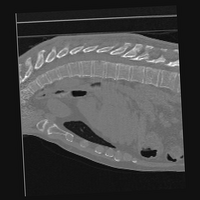

Exp. 3: Adult thorax data: To show the versatility of our approach we also apply it to adult thorax scans. For this experiment no organ specific training is performed but the whole volume is used. We evaluate reconstruction performance similar to Exp. 1 and prediction performance when is projected on an external plane, comparable to X-Ray examination using C-Arms. The latter provides insights about our method’s performance when applied to interventional settings in contrast to motion compensation problems. 60 healthy adult thorax scans were randomly selected, 51 scans used for and nine scans used for . Each scan is intensity normalised and resampled in a volume of with spacing . Using the Fibonacci sampling method, 25 sampling plane of size , evenly spaced between -50 and +50, were rotated over 500 normals. Training took approximately 20 hours for 60 epochs. Fig. 4c shows an example reconstruction result gaining 28dB PSNR with additional SVR. prediction takes approx. 20 ms/slice for this data.

0..5.3 Exp. 3:

We replicated the experiment on adult thorax data without specifically segmented organs. This approach was applied to CT acquisition, shown in Fig 13 and 14, as well as Digitally Reconstructed Radiographs generated using Siddon-Jacobs Ray Tracing shown in Fig. 16.